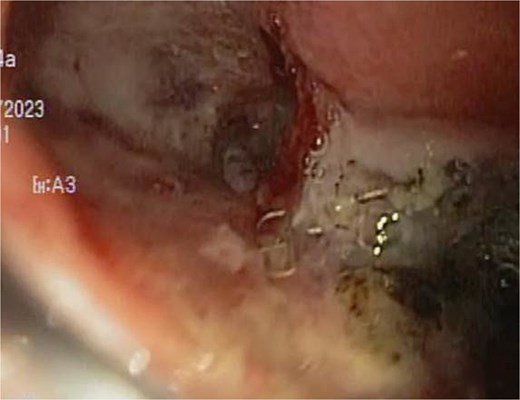

A 48-year-old female without comorbidities underwent vertical sleeve gastrectomy for grade II obesity, developing a leak in the upper third of the sleeve, presenting with a productive cough. Endoscopy revealed a 15 mm fistula (Fig. 6). EVAC therapy was initiated with changes every 3–5 days (Fig. 7). The patient showed slow evolution, developing an intragastric abscess and productive cough. After nine changes over 45 days, endoscopy showed complete resolution of the fistula (Fig. 8).

Initial endoscopy shows a fistulous defect below the gastroesophageal junction.

A sponge replacement is performed, revealing a fistulous opening with granulation tissue.